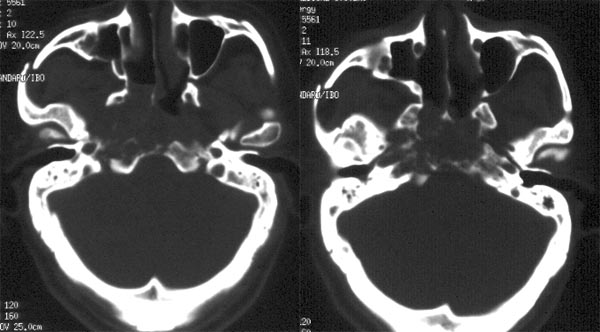

患者放疗后半年ct复查

ct平扫:鼻咽右侧壁增厚,右侧咽隐窝消失,右侧咽旁间隙变窄,但病灶较原片明显缩小。原片所见鼻咽顶壁、顶后壁、后壁增厚,现已基本恢复正常,原片见枕骨斜坡、蝶骨基底部骨质破坏,现亦已修复,为高密度骨质充填。颈深筋膜各间隙未见肿大淋巴结。

ct诊断:鼻咽癌放疗后,肿物较前片明显缩小,颅底骨质破坏基本修复。